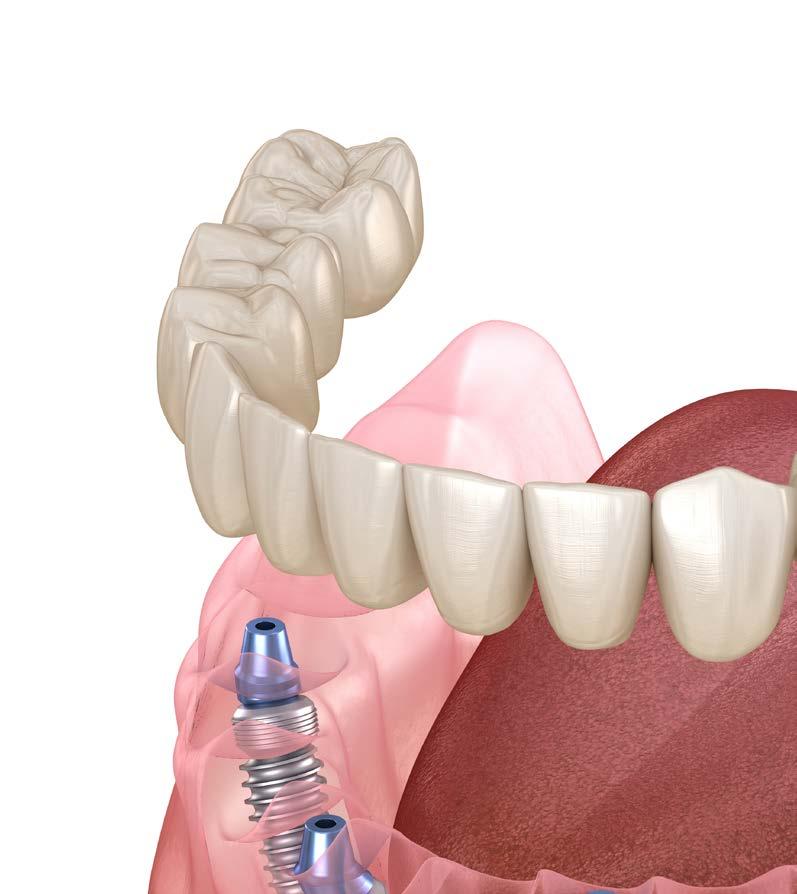

con gran pérdida de soporte.4-5 Por lo tanto, los pacientes que padecen esta enfermedad suelen ser candidatos a tratamientos de rehabilitación para reemplazar las piezas dentales perdidas. Tradicionalmente, estas reposiciones se realizaban mediante prótesis removibles o prótesis fijas apoyadas en dientes naturales. Sin embargo, en la actualidad, los implantes dentales se han convertido en la opción de tratamiento más solicitada por este grupo de pacientes. 5-6 En cuanto al plan de tratamiento integral para los pacientes con periodontitis, sobre todo las agresivas, que se dan en pacientes de menor edad, existen diferentes enfoques sobre la rehabilitación con implantes. Algunos estudios abogan por mantener los dientes que puedan ser salvados, siempre que no comprometan la rehabilitación con implantes, mientras que otros recomiendan extraerlos para evitar efectos adversos sobre los implantes.7-11 En pacientes con periodontitis agresiva, la

consideración que cuando la patología periodontal avanza, se genera una pérdida ósea que produce una atrofia ósea marcada, lo que a su vez produce que la rehabilitación posterior con implantes sea más compleja, por lo que para estas situaciones, poder disponer de diferentes técnicas quirúrgicas e implantes de distintos

diámetros y longitudes que nos permitan un abordaje más conservador de la zona a tratar son diferenciales, así como el tratamiento concomitante de las zonas edéntulas y las zonas con EP activa para lograr un buen resultado final que satisfaga al paciente y al profesional.17-18 Para el abordaje de la pérdida de altura ósea

en el sector posterior, clásicamente se han empleado 2 técnicas: la elevación de seno tradicional o convencional (mediante ventana lateral) y modificaciones llevadas a cabo a través de la cresta (transcrestales), más

conservadoras y más extendidas en la actualidad en rebordes óseos que presenten al menos 3-4 mm de altura residual.19,20 Aunque cada uno de estos procedimientos tiene indicaciones clínicas bien definidas según

la altura ósea residual, la comparación de ambas técnicas en pacientes con casos más complejos, como aquellos que padecen periodontitis agresiva, puede resultar especialmente relevante.20-21 En este caso clínico, mostramos la evolución a lo largo del tiempo de 2 técnicas diferentes (elevación de seno convencional y transcrestal) aplicadas en un mismo

paciente con periodontitis agresiva.

Se ha realizado un seguimiento de los implantes colocados mediante ambos procedimientos, bajo las mismas condiciones clínicas, lo que permite comparar su comportamiento en el mismo paciente con el paso del tiempo y extraer conclusiones sobre el comportamiento de los 2 protocolos de tratamiento.